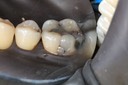

Kyle Chock #14 pre-op